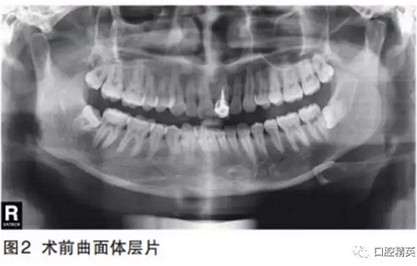

曲面體層片示21已行根管治療并樁冠修復。牙周膜正常,根尖無暗影,遠中牙槽嵴頂骨質(zhì)略吸收1mm。